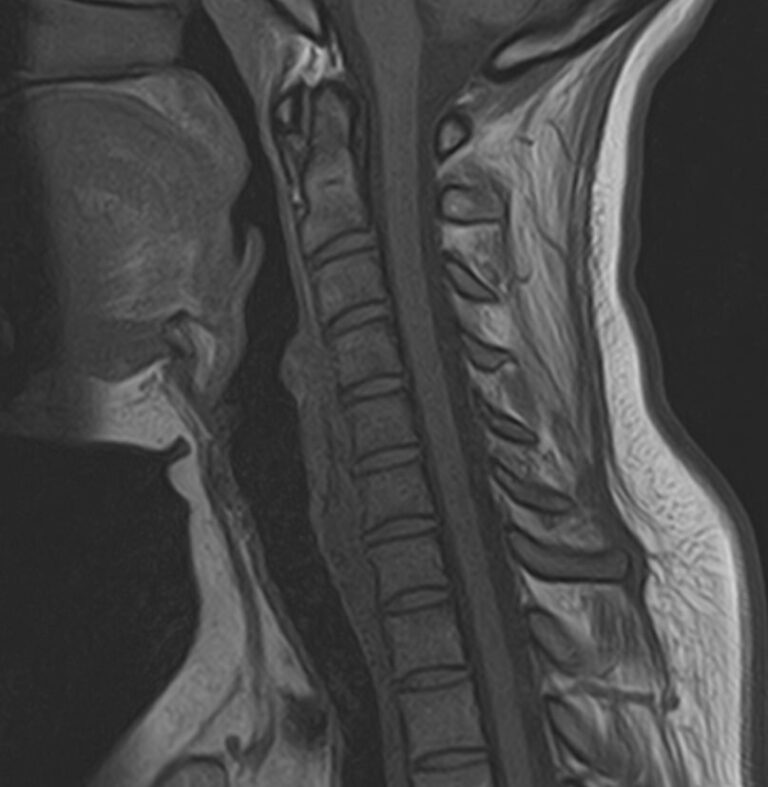

Шейный отдел позвоночника — это самый подвижный сегмент позвоночного столба, который испытывает повышенные нагрузки, подвержен травмам и развитию различных заболеваний. В эту анатомическую область входит 7 верхних позвонков, спинной мозг с отходящими от него нервными корешками, а также проходят крупные сосуды, кровоснабжающие головной мозг.

МРТ шейного отдела позвоночника позволяет проводить диагностику дегенеративных заболеваний позвоночного столба (в том числе межпозвонковых грыж, протрузий, остеохондроза), выявлять воспалительные, травматические изменения и объемные образования в области шейных позвонков и спинного мозга.

В клинике «Доступная медицина» данное исследование проводится на современном высокопольном магнитно-резонансном томографе экспертного класса TOSHIBA VANTAGE TITAN 1,5 Тесла. Напряженность магнитного поля 1,5 Тесла обеспечивает высокую разрешающую способность аппарата, что позволяет выявлять минимальные изменения в тканях и диагностировать заболевания на начальной стадии.